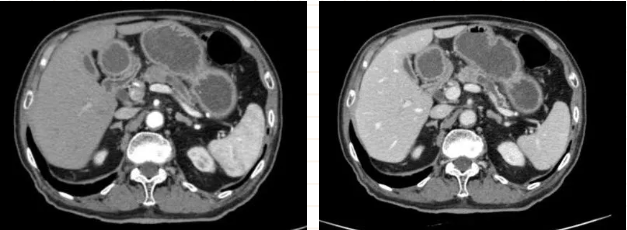

陈艳军主任团队在了解情况后,将白先生收治入院,并进一步完善相关检验检查。上腹部增强CT检查示:胰体部乏血供占位,较大横截面约1.8*1.6cm,伴周围稍大淋巴结,考虑恶性胰腺癌,以远胰管扩张。